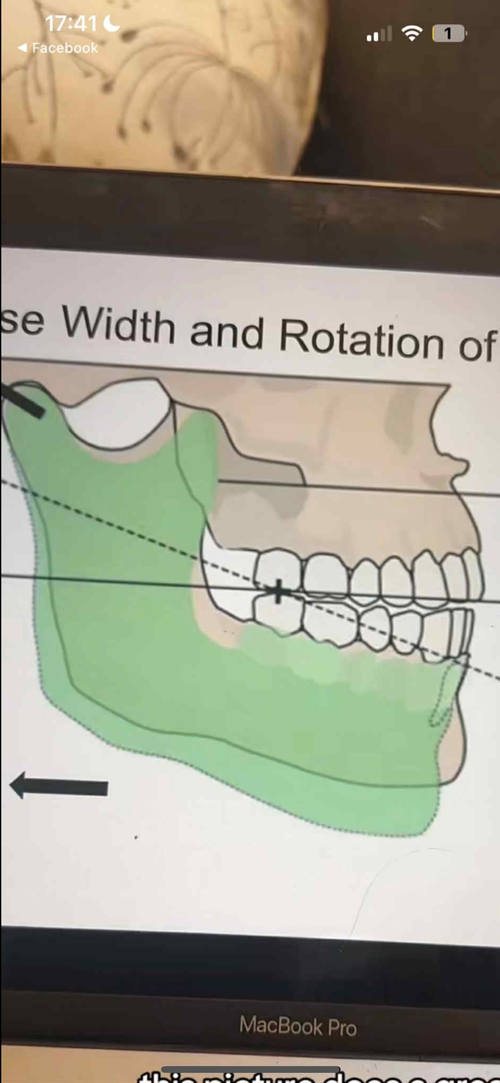

- The harsh true is that once the sutures are fractured from the expansion and the beloved SKelEtaL expansion occurs, your maxilla will rotate in a clockwise rotation(see video).

From an aesthetic perspective this is just horrible. Your soft tissue drops, your orbit support decreases, your face are lengthen and your mandible move backwards(see image 2 what happends when clockwise occurs). There are several more hits on the aesthetics from the clockwise rotation but this post will be too long if I go into too much details.

- The harsh true is that once the sutures are fractured from the expansion and the beloved SKelEtaL expansion occurs, your maxilla will rotate in a clockwise rotation(see video).

From an aesthetic perspective this is just horrible. Your soft tissue drops, your orbit support decreases, your face are lengthen and your mandible move backwards(see image 2 what happends when clockwise occurs). There are several more hits on the aesthetics from the clockwise rotation but this post will be too long if I go into too much details.